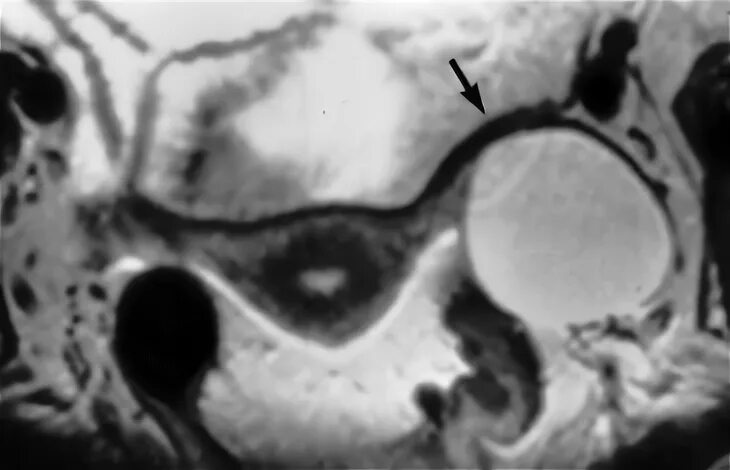

Солидные образования малый таз